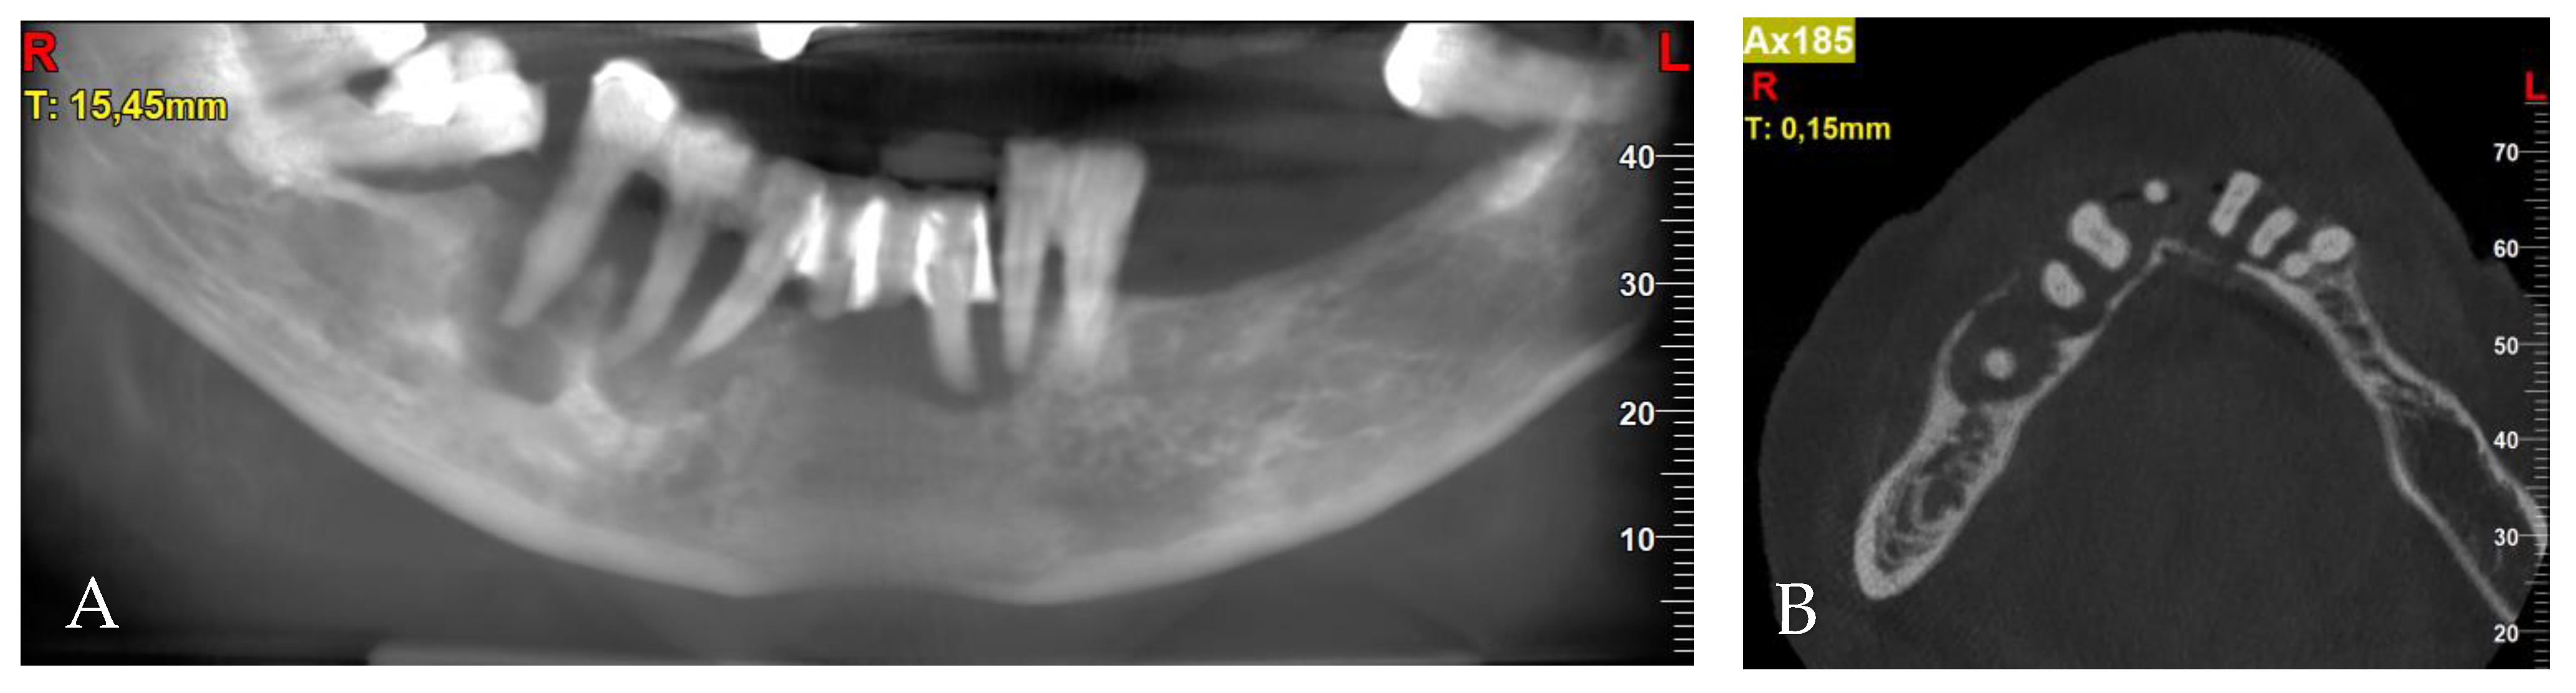

3.1. Patient Information, Diagnosis and Treatment Plan

3.2. Surgery 1—Teeth Extraction and Periodontal Lesion Enucleation with Simultaneous Implantation